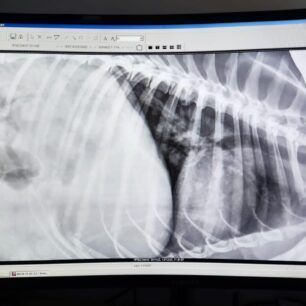

Οι ακτινογραφίες έδειξαν τους όγκους παντού στο σώμα του ζώου…